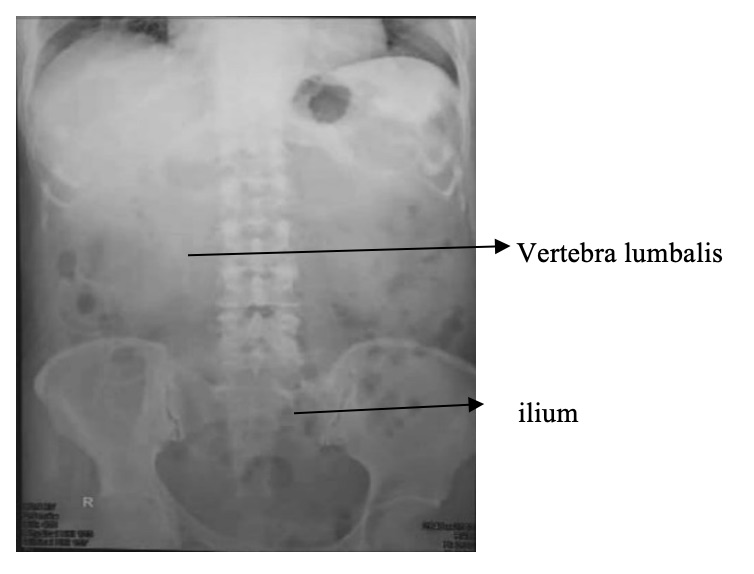

Figure 2. Kriteria Gambar Proyeksi AP (Plain Foto)

Lakukan injeksi 5 cc media kontras melalui kateter menuju renal pelvis, pada ginjal yang diperiksa.

- Diambil dengan menggunakan film ukuran 24 x 30 cm

- Kontras dimasukkan kembali ± 5 cc sambil kateter ditarik perlahan, lalu foto, menggunakan film ukuran 24 x 30 cm untuk melihat ureter

- Kontras dimasukkan sampai habis, sambil ditarik di perkirakan kontras habis, foto diambil dengan menggunakan film ukuran 24 x 30 cm